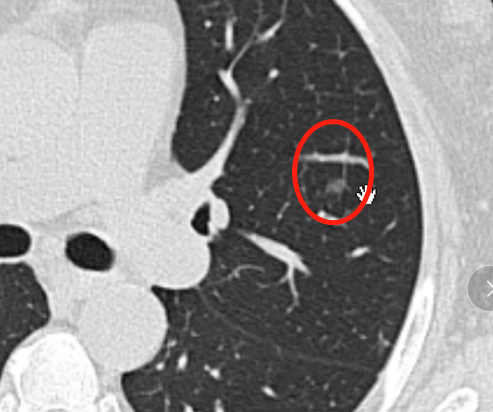

肺结节,恐怕是当今体检当中最让人纠结的一个小东西了。基本都是CT发现,尤其是一公分上下的,或明或暗,或半透明或实心儿,就像太空中一个外来星体,默默地呆在那里,让人始终揪着心。它到底是好是坏,会不会癌变,很难说清楚。 实在拿不准的,只能用时间来让它暴露。毕竟,人类还是更聪明。只要它沉不住气发生某些变化,就会被医生发现蛛丝马迹,斩于马下。 首都医科大学附属北京胸科医院胸外一科副主任医师杨志,跟我们分享了这样一个病例。这位女性患者自己也是医务工作者,53岁,六年前CT发现一个肺结节。刚发现的时候也确实拿不准,耐心地观察六年之后,一根小血管把这个结节的恶性本质暴露了。 这位患者是怎么发现的结节? 杨志:体检发现。因为她本身就是从事医疗行业,所以对自身的健康比较关注,每年都会做体检。六年前发现了左上肺叶的一块微结节的病灶。结节旁边有一支血管,这是一个可疑的血管滋养支,不是很明显,比较淡。 就说有一根小血管跟这个结节连在一起? 杨志:对,连在一起。大概0.8cm、0.9cm这个样子。 0.8cm、0.9cm,将近一公分了? 杨志:最长径不到一公分。 这其实在结节里头算是相对小的了? 杨志:对,应该叫微结节,算是最小的微结节,长径大概有0.9cm。 根据这个结节的形态,你们怎么判断它有没有问题呢? 杨志:首先在影像上,这块局部的微结节并不能判断是肺癌,但是我们根据增强CT扫描,又发现形成了供应营养的血管,癌的可能性就增加了。 就是说它连着跟血管的危险性就比较大了? 杨志:对,风险比较大。但是因为结节本身比较小,其实0.8cm、0.9cm这个体积的话,相对于肺内结节属于最早期的一个微结节,这种小于一公分的微结节,原则上是可以观察的。 那您建议她观察多长时间? 杨志:我建议她一年之后再复查。 那病人自己有没有表达担心,这结节一年以后会不会变? 杨志:也有担心。所以初期发现结节的话,如果病人也表示了比较明显的担心,那我们可以把检查周期缩短到半年,太近就不好了,就没有意义了,没有必要。另外病变的结节,是有一个变化的规律的,一般来说不会出现迅猛的增加。 那这位病人一年以后的情况呢? 杨志:一年之后其实也没有特别大的变化,还是那个样子,所以她一直在观察,保持间隔一年观察一次的频率。 她后来观察到什么时候? 杨志:观察到近期,近期是第6年的复查。第6年的复查图像我们发现异常了,病变比之前要变大了一些,而且颜色变深,密度增加。而且其中在血管进入的位置有一块稍白的部分,这说明有可能出现了浸润灶——浸润灶是癌细胞比较富集的位置,可能开始有往外的侵袭了。 就是癌细胞可能突破了原来“小球球”? 杨志:它也在这个“球”之内。在这个“球”之内,癌细胞开始往外渗透,我们在病理学上叫微浸润——微浸润就是对周围的组织开始出现侵袭性成长了。如果出现了微浸润的情况,就说明癌细胞有可能在近期内出现非常大的发展,往外扩增,就有可能出现转移。 就是从影像上“稍白”的部分可以看出它向外侵袭了? 杨志:对,这个地方比其他部分深一些,而且这只供养支血管比之前变粗了。供养支变粗了,肿瘤的内部又出现了实性灶,就说明癌的浸润性增强了。之前它可能是原位,它现在有可能变成在病理学上称作“微浸润性腺癌”的一种特殊的类型。影像上尽管不能确诊,但是我们长期经验还是高度怀疑的,必须警惕。 也就是这个结节有向外扩张的倾向,具备了恶性的特征? 杨志:对,基本上恶性的可能性非常大了。而且在出现微浸润性病灶的时候,它可能会出现一个比较迅猛的增长期,加上有血管的供养,这种增长期,有可能出现癌细胞脱落,顺着血管就流到全身其他器官了,有转移的风险,起码转移到淋巴结的风险要增加。而肺内淋巴结转移的情况,和生存期是非常相关的。 我们在临床上判断一个结节肺内结节,主要是一公分为限:小于一公分、一公分到两公分、两公分到三公分、超过三公分分成不同限度。在小于三公分的情况下,尤其1~2公分甚至小到1公分的情况下,5年生存率在微浸润腺癌的病理类型算,接近100%。 就是手术以后可以治愈了? 杨志:基本彻底治愈。而且我们所说的“5年生存率100%”是指无症状、无病患,是生活质量非常高的状态,因为相对来说体内无病。而且5年生存率高的话,后续的10年生存率、15年生存率都会非常高。 如果错过了这个时机,病变超过了一公分,或者达到两公分等等,它的5年生存率只能达到84%,降了很多,但是依然可以接受,84%也算相对较高的数字;如果再继续增加,达到2~3公分左右,这种情况只能达到60%多,65%左右,概率就非常低了。 60%多的生存率,是在用了各种治疗手段的情况下,化疗、放疗、靶向各种手段全用上,也不过是60%? 杨志:对,全部用上。另外在早期其实也不是特别建议使用这么强的手段,比如说化疗、免疫治疗,现在方法很多,但是一般来说不会用于早期患者,一般来说都是,出现问题之后,比如复发、转移,出现进展了,我们再用这些比较强力的“拳头”或者是方式。但是即使用了这种强力的方式,这种2~3公分的结节5年生存率还是不如人意,可能只有60%多。 假设出现了比较大的大块,5公分左右,甚至于更严重的情况,那么5年生存率非常迅速地降到50%以下,只有40%多。 这个不到一公分肺结节的患者,后来你们是怎么治疗的? 杨志:我们做微创手术把它切除了。做了个肺叶切除,淋巴结也清扫了,最终的病理报告提示微浸润性腺癌,跟我们术前影像判断的一样,而且淋巴结没有转移。这种情况对于她来说是非常好的,基本上就是5年生存率接近100%。 最后,杨志医生强调,这个患者6年前的结节就发现了细小的血管,并不能证明它就是恶性。良性肿瘤也可能有这样的现象。肺结节的处置,原则就是“不放过一个坏人,但也不能冤枉一个好人”,手术之前,尽量取得这个结节是恶性的证据,证据不明确,在确保安全的情况下,能不开刀就不开刀,尽量保全患者的健康肺。 肺结节手术,是个技术活儿,也是个良心活儿。